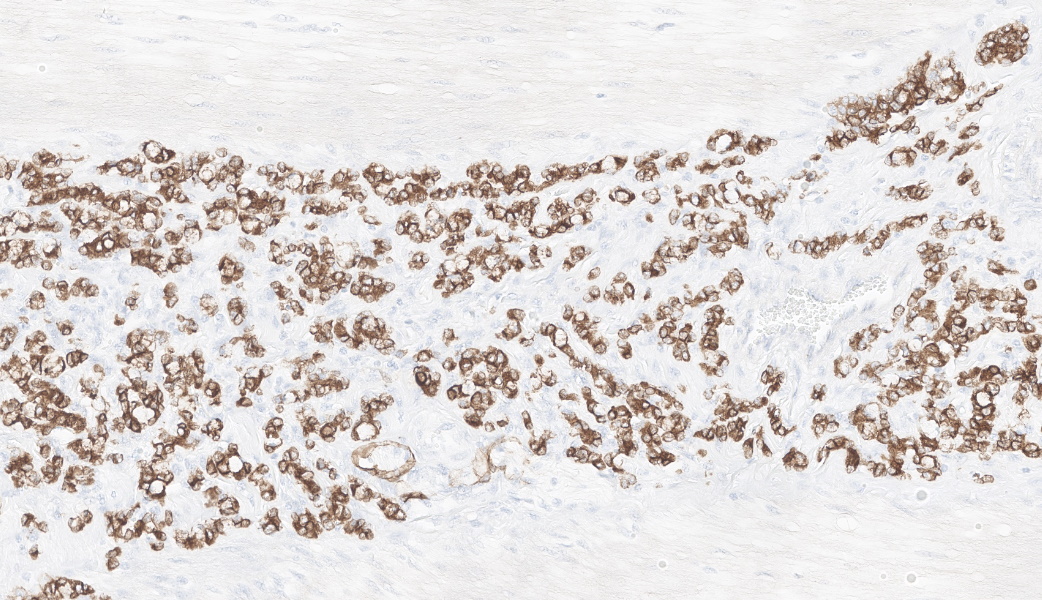

Colon: The lamina propria, submucosa, muscularis mucosa and serosa are markedly expanded by a poorly demarcated, non-encapsulated, infiltrative neoplasm composed of two populations of neoplastic epithelial cells. The neoplastic cells occur singly and in loose packets, lobules and cords, and are supported by variable fibrous stroma containing fibrocytes, fibroblasts and a light basophilic matrix. The predominant neoplastic cell is round to ovoid, 20–50 μm in diameter, with distinct cell borders, abundant finely granular basophilic cytoplasm, peripherally located oval nuclei with lightly stippled pale chromatin and single nucleoli. The secondary type of neoplastic cell is round to oval; 15-30 μm in diameter; with distinct cell borders; moderate amounts of cytoplasm containing small eosinophilic granules; single, peripherally located, large nuclei with coarse chromatin and single nucleoli. Both sub-populations of neoplastic cells exhibit moderate anisocytosis and anisokaryosis. Mitoses are rare (< 1 per HPF). There is moderate expansion of the adventitia of large vessels with neoplastic cells. The lamina propria propria is diffusely expanded by moderate numbers of lymphocytes, plasma cells, occasional macrophages and rare eosinophils. Crypts are often ectatic, lined with attenuated epithelium and containing non-degenerate neutrophils, rare macrophages and lymphocytes (crypt abscess).

- Large intestine, colon: Intestinal adenocarcinoma, sheep (Ovis aries), ruminant.

Ileocecal junction: Intestinal adenocarcinoma.

This last case is a classic! Many thanks to the contributor for a great submission and write-up. Most participants were readily able to reach a diagnosis of intestinal adenocarcinoma in this case due to the high mitotic rate, degree of invasion the neoplasm into abluminal tissue layers, and the striking desmoplastic response. The deep infiltration from the mucosa outwards allows for a strong argument of a primary intestinal adenocarcinoma rather than a metastatic carcinoma. Intestinal adenocarcinomas tend to invade from the mucosa deep into and run laterally through the submucosa and subsequent layers.

In sheep, the primary ruleout would be metastatic uterine adenocarcinoma, but this would more likely present on the serosal surface due to direct seeding of the abdomen (carcinomatosis) or via lymphatic spread rather than invading from the mucosa. Additionally, intestines are not a primary site for lymphatic metastases for uterine adenocarcinoma in most species; the lungs, liver, and mesentery, however, are.3 Although generally considered an incidental finding at slaughter, previous studies have demonstrated an increased incidence of intestinal adenocarcinoma in sheep in New Zealand following exposure to feedstuffs sprayed with phenoxy and picolinic acid herbicides.10